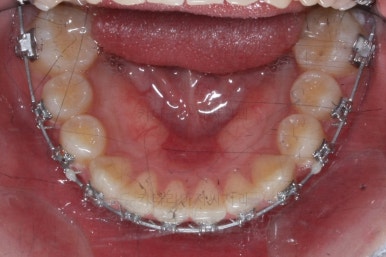

아무래도 치아 크기의 문제가 있다보니 완벽한 교합을 맞추기는 힘들었짐나 가능한 마무리를 더 해보기로 했어요.

마무리 때의 모습입니다.

임시 개념으로 치아 사이즈를 키운건데 환자분은 만족하시나봐요.

보통 올세라믹, 라미네이트 등 보철치료는 성인이 되어서 해야해서 이래나 저래나 이정도에서 만족하기로 했습니다.

치아는 매우 가지런해졌고 뾰족하던 앞니의 형태도 좋아졌어요.

매복되어 있던 송곳니도 잘 나왔고 과개교합도 물론 개선이 되었습니다.